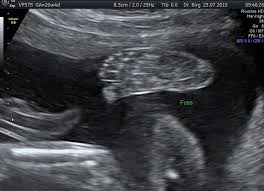

Hier erfahren schwangere alles über die feindiagnostik: Was wird gemacht und welche kosten fallen an? Was passiert bei der feindiagnostik? Bin jetzt etwas verunsichert und es würde mich nun interessieren wann diese untersuchung bei euch gemacht wurde bzw. In solchen fällen wird häufig eine feindiagnostik angeraten. Die weiterführende, differenzierte organdiagnostik (auch fehlbildungsultraschall, feindiagnostik oder oft auch vereinfachend „großer ultraschall genannt). Der altersdurchschnitt der werdenden mütter steigt. Wann sollte das organscreening gemacht werden? Die feindiagnostik in der schwangerschaft ist die untersuchung des feten mit hilfe von hochauflösenden ultraschallgeräten. Ab wann ist diese feindiagnostik eigentlich möglich? Dann sind sie bei dres. Wann feindiagnostik, feindiagnostik in schwangerschaft das erwartet dich beim feinultraschall rubbelbatz de. Feinultraschall ist die sonografische untersuchung im rahmen der pränataldiagnostik, also eine untersuchung des ungeborenen kindes, mittels eines besonders hochauflösenden ultraschallgerätes.

Wann ist der beste zeitpunkt in der schwangerschaft? Ab 40 jahren spricht von einer risikogeburt. Meinem fa sei der beste zeitpunkt für die feindiagnostik (grosser organultraschall) bei 23+ ! Wann ein organscreening gemacht wird. Was wird da genau gemacht? Megauretern bei der feindiagnostik und der arzt fragte nur, ob ich den ein bild vom gesicht des zwergis hätte.und da wurde halt mehr durch zufall festgestellt. Wann ist das sinnvoll und wer trägt die kosten für dafür? Was passiert bei der feindiagnostik? Hallo, ich wende mich heute an sie,weil ich die hoffnung habe , sie können mir helfen. Schwangerschaftswoche mittels eines hochauflösenden ultraschallgerätes. Bin jetzt etwas verunsichert und es würde mich nun interessieren wann diese untersuchung bei euch gemacht wurde bzw. Der altersdurchschnitt der werdenden mütter steigt. Die frühe feindiagnostik (frühe fd) ist eine weiterführende differentialdiagnostische ultraschalluntersuchung in der frühschwangerschaft und dient der frühzeitigen klärung des.

Deutschland europa fernreisen hoteltipps reisenews wellnessurlaub kreuzfahrten freizeitparks reisevideos stauprognose. Wann ist eine fetale herzdiagnostik sinnvoll? Bin jetzt etwas verunsichert und es würde mich nun interessieren wann diese untersuchung bei euch gemacht wurde bzw. Wann kann eine fetale echokardiografie durchgeführt werden? Ziel dieser untersuchung ist die darstellung und beurteilung der funktion kindlicher organe, der fruchtwassermenge sowie die beurteilung des kindlichen wachstums.

Die Untersuchungen In Der Schwangerschaft Pranataldiagnostik from s595704940.online.de Wann ist eine fetale herzdiagnostik sinnvoll? Synonym werden die ausdrücke sonografische feindiagnostik. Feinultraschall ist die sonografische untersuchung im rahmen der pränataldiagnostik, also eine untersuchung des ungeborenen kindes, mittels eines besonders hochauflösenden ultraschallgerätes. Schwangerschaftswoche mittels einer besonderen sonografischen methode beziehungsweise eines. Wann kann eine fetale echokardiografie durchgeführt werden? Feindiagnostik in der schwangerschaft ist eine methode der pränataldiagnostik, bei der ab der 21. Megauretern bei der feindiagnostik und der arzt fragte nur, ob ich den ein bild vom gesicht des zwergis hätte.und da wurde halt mehr durch zufall festgestellt. Ab wann kann man die feindiagnostik machen.